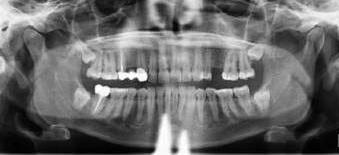

Panel Ahli American Dental Association (ADA) mengeluarkan rekomendasi baru terkait peningkatan keamanan prosedur radiograf. Rekomendasi ini mengemukakan bahwa penggunaan apron timbal dan pelindung tiroid tidak lagi direkomendasikan. Rekomendasi ini diterbitkan dalam The Journal of the American Dental Association pada tanggal 1 Febuari 2024 yang bertujuan untuk meningkatkan perlindungan proteksi radiasi pada radiografi dental dan CBCT.

Dalam rekomendasi ini, panel ahli meninjau beberapa publikasi terhadap radiograf, dimana penggunaan apron dan pelindung tiroid tidak lagi diperlukan untuk mleindungi pasien dari paparan radiasi. Rekomendasi ini berlaku bagi seluruh pasien dengan tidak memandang umur dan status kesehatan seperti kehamilan.

Dari beberapa bukti yang dikumpulkan, peralatan radiografi modern saat ini sudah dibekali kemampuan utnuk membatasi ukuran sinar X terbatas hanya pada area yang diinginkan untuk pencitraan yang baik serta melindungi bagian tubuh lain dari paparan radiasi. Dari bukti ilmiah tersebut disebutkan bahwa penggunaan apron dan pelindung tiroid menghalangi sinar X primer sehingga hasil pencitraan yang dibutuhkan menjadi kurang baik. Jika hal ini terjadi, maka diperlukan pengambilan radiografi ulang sehingga menambah paparan sinar radiasi yang seharusnya tidak diperlukan.

Kepala bagian Departemen Periodontology dan Oral Medicine University of Michigan School of Dentistry , Dr. Purnima Kumar, D.D.S., Ph.D dan Panel Ahli ADA mengatakan, rekomendasi ini menjadi imbauan bagi klinisi dalam melakukan tindakan radiografi yang terukur dan tidak terlalu banyak untuk meminimalisir paparan radiasi pada pasien, dokter, serta perawat gigi.

ADA juga mengeluarkan rekomendasi untuk menghindari paparan radiasi dengan beberapa cara, yaitu :

1. Melakukan tindakan radiografi dengan tujuan untuk mengoptimalkan informasi diagnostik dan meningkatkan hasil perawatan pasien serta sebisa mungkin menggunakan gambar radiograf pada pemeriksaan gigi sebelumnya

2. Menggunakan mesin radiografi digital dibandignkan mesin radiografi konvensional

3. Membatasi area paparan sinar X hanya pada daerah yang perlu dilihat

4. Memposisikan pasien dengan benar sehingga meminimalisir kesalahan pengambilan gambar atau gambar yang kurang tepat

5. Menambah opsi penggunaan CBCT hanya jika opsi radiograf lain dengan paparan rendah tidak dapat memberikan informasi diagnostik yang diperlukan

6. Mematuhi peraturan terkait radiasi yang berlaku di daerah setempat.

Hingga saat ini, rekomendasi ini masih belum dapat di terapkan di Indonesia karena belum adanya perubahan peraturan sehingga penggunaan apron dalam praktik radiologi masih diperlukan [medicalxpress.com, M.Syauqi]